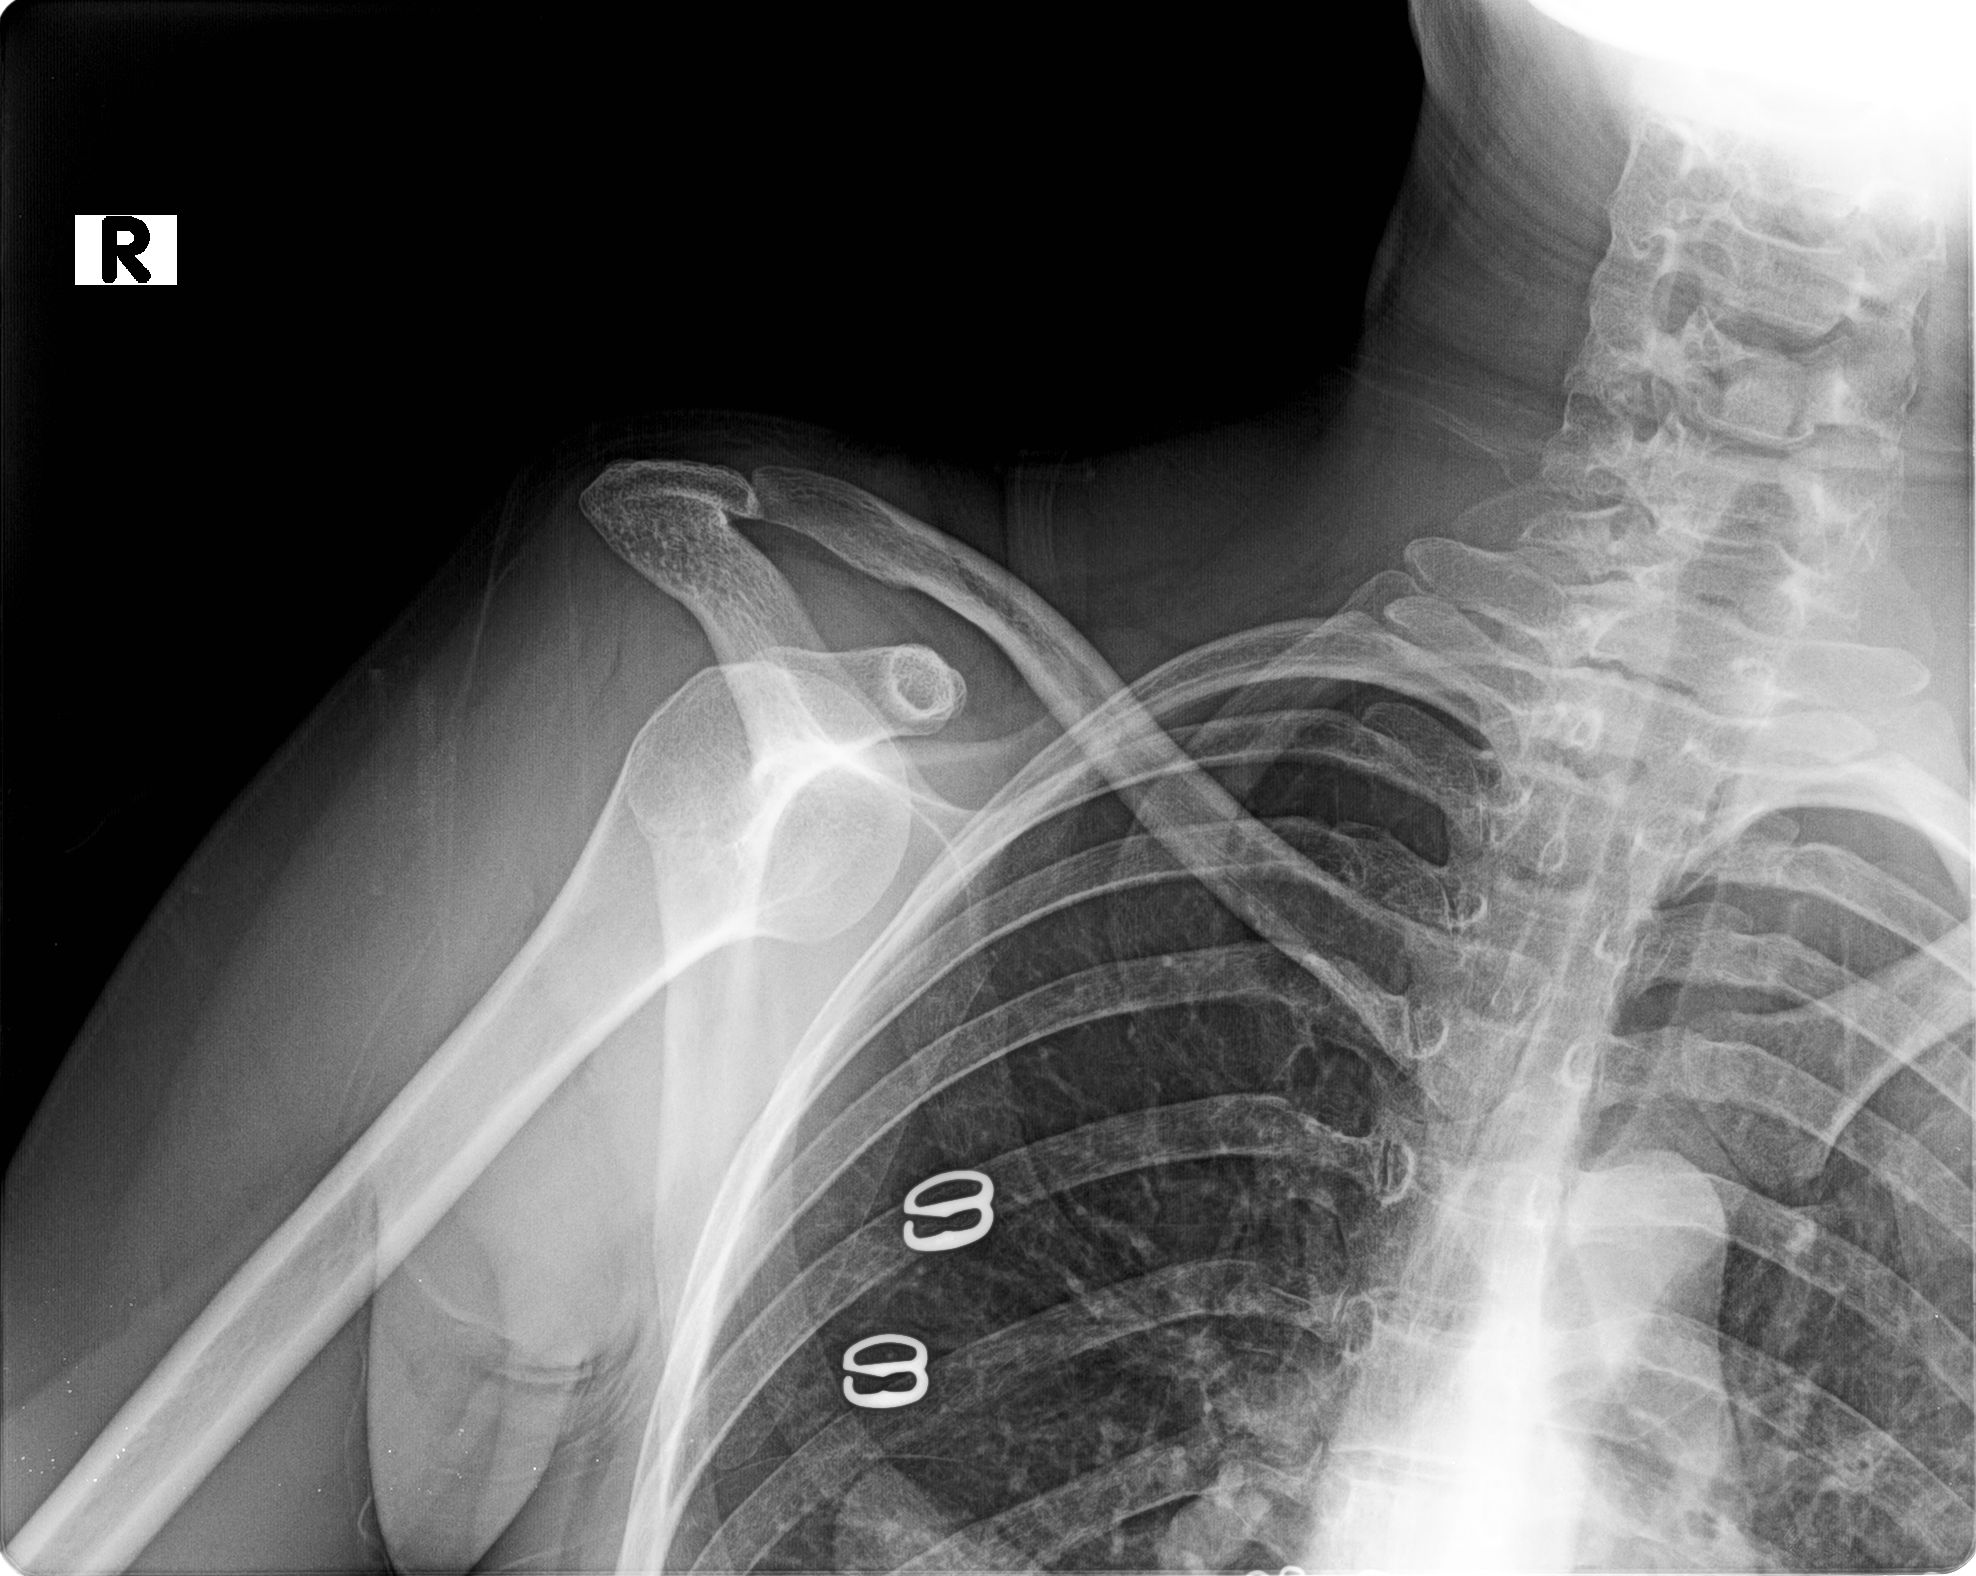

Travmatik omuz çıkığı örneği: